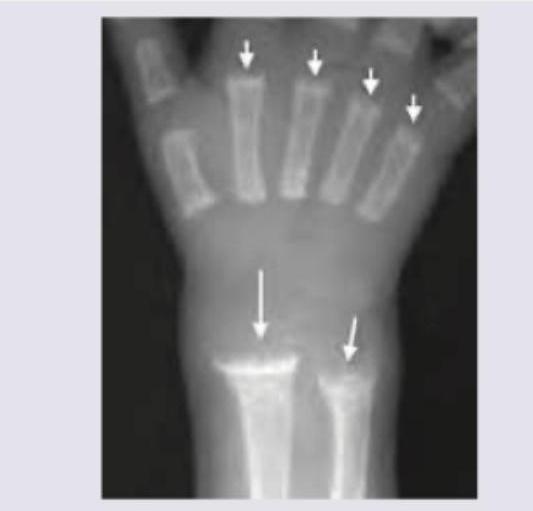

A 2-year-old child presents with delayed motor milestones and bowing of legs. X-ray of the wrist is shown. What is the most likely diagnosis?

Explanation: ***Rickets*** - The image displays characteristic radiographic findings of **rickets**, including **fraying, cupping**, and **widening of the metaphyses**, particularly evident at the distal radius and ulna. - These changes result from impaired mineralization of growing bone and cartilage at the **growth plates** due to vitamin D deficiency in children. *Scurvy* - Scurvy, caused by vitamin C deficiency, affects **collagen synthesis**, leading to subperiosteal hemorrhages and thinning of the cortex. - Radiographic features include a **dense metaphyseal line (Wimberger's sign)** and **epiphyseal separation**, which are not the primary features seen here. *Osteomalacia* - **Osteomalacia** is the adult form of rickets, characterized by defective mineralization of bone matrix. - While it features **pseudofractures (Looser zones)** and generalized osteopenia, it does not present with growth plate abnormalities like fraying and cupping, as growth plates are typically closed in adults. *Osteoporosis* - **Osteoporosis** involves a reduction in bone mass and density, leading to increased bone fragility and fracture risk. - Radiographically, it manifests as generalized **osteopenia** and trabecular thinning, without the specific metaphyseal irregularities seen in rickets.